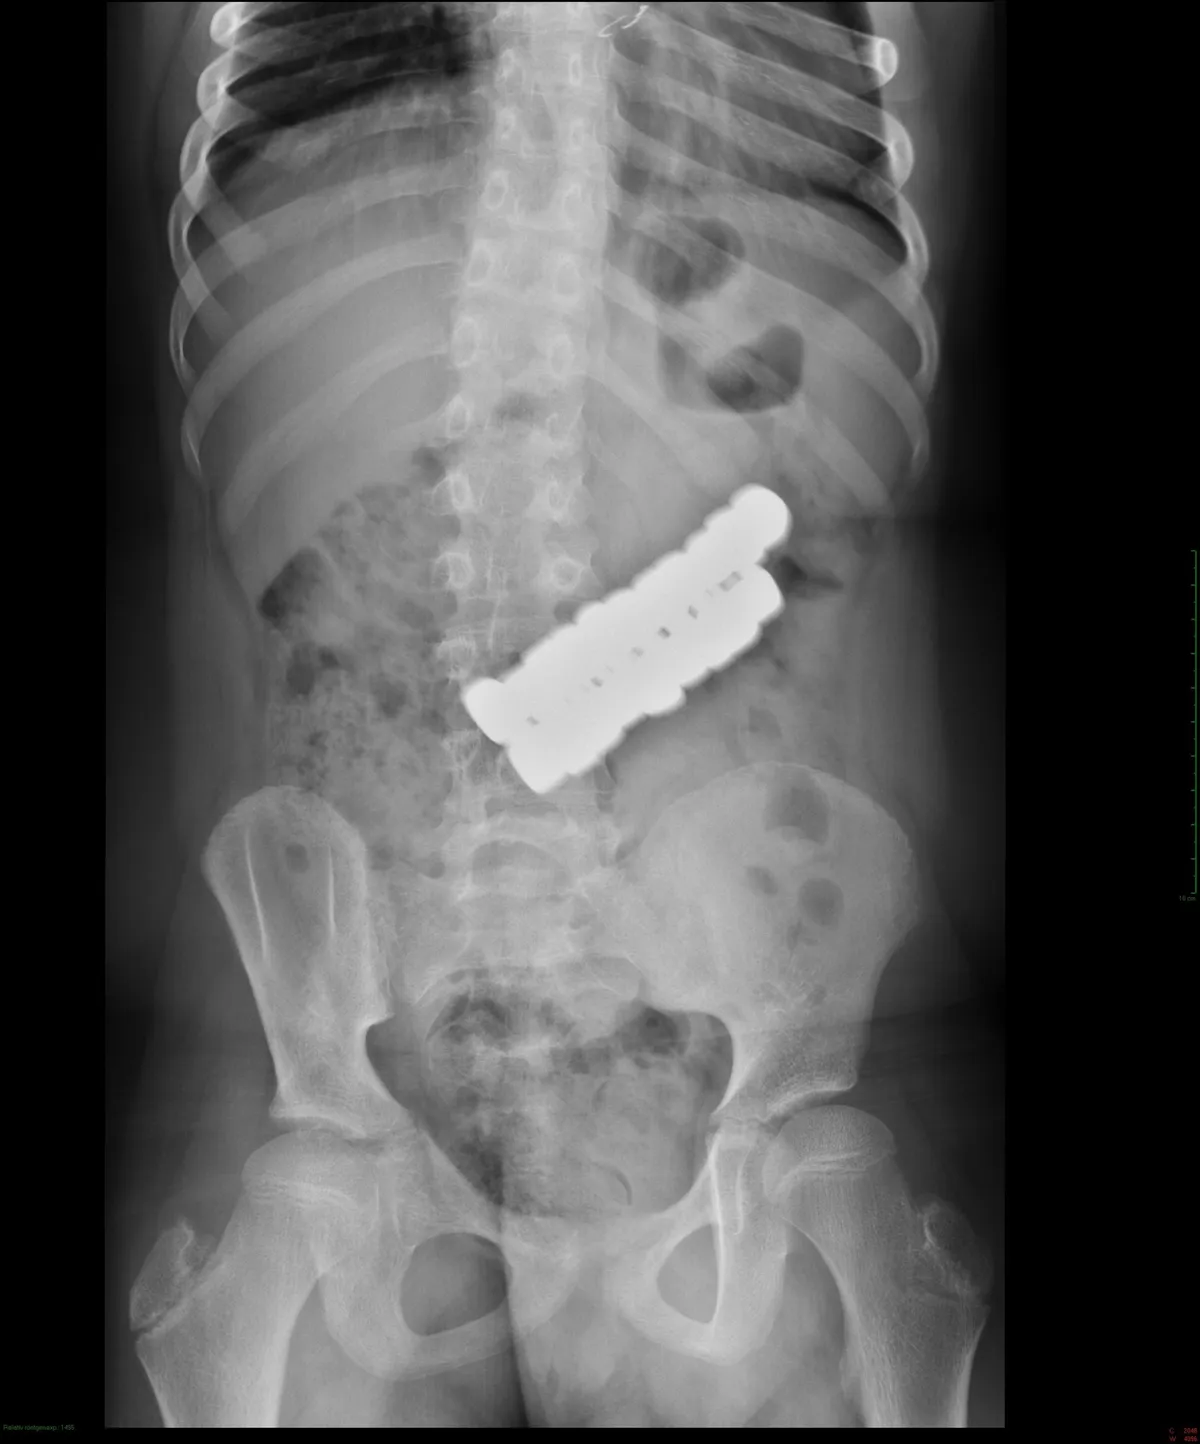

„Ennél a gyermeknél időben derült ki, mi történt, és a mágnesek még azelőtt eltávolíthatók voltak, hogy a belekben súlyos, visszafordíthatatlan károsodást okozhattak volna” - írták a Facebook-bejegyzésben. A kórház weboldalán olvasható, hogy a 10 éves kisgyermek miután lenyelte a 20 darab mágnest, nem tapasztalt semmiféle fájdalmat. A kórházban röntgenfelvételeket készítettek, amin jól látható volt, ahogy a mágnesek egy csomóban, egymáshoz kapcsolódva helyezkedtek el a kisgyermek gyomrában. A mágneseket sajnos egyenként nem tudták eltávolítani, így műtétre került sor.